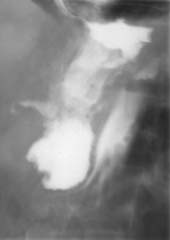

4. Больной З., 47 лет, страдающий хроническим панкреатитом, поступил в хирургию

с наличием гнойного свища на заднебоковой поверхности брюшной стенки. В анамнезе

у больного произведено оперативное вмешательство, заключающееся в наложении

цистогастроанастомоза (анастомоз между кистой поджелудочной железы и желудком),

после которого больной чувствовал себя хорошо. Однако наличие свища позволило

предположить облитерацию анастомоза. Одновременное исследование желудка и введение

контраста в свищевой ход подтвердило это предположение (Рис. 4).

Рис. 4. Выполнена фистулография (контраст в ретрогастральном

пространстве) и контрастирован желудок. Ранее наложенный анастомоз

между кистой поджелудочной железы и желудком не контрастируется.